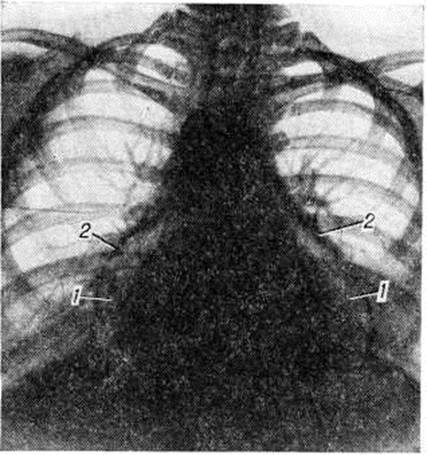

Рис. 6.

Экссудативный Перикардит в начале своего развития проявляется изменением конфигурации сердечной тени за счёт выпрямления талии сердца; в дальнейшем она может стать даже выпуклой. По мере накопления выпота сердечная тень становится все более сферической, силуэт сердца теряет свою дифференцировку на дуги, отмечается быстрое увеличение тени сердца с превалированием её поперечного размера над длинником, смещение вправо дуги правого предсердия. Исчезает тень нисходящей части аорты, сосудистый пучок расширяется за счёт верхней полой вены и представляется относительно укороченным. Кардиодиафрагмальные углы, особенно правый, заостряются. При повторных исследованиях отмечается быстрая динамика увеличения размеров тени сердца. При изменении положения тела форма сердечной тени меняется. Амплитуда пульсации контуров сердца уменьшается вплоть до полного её исчезновения при сохранении пульсации крупных сосудов. Лёгочный рисунок остаётся нормальным, несмотря на выраженное увеличение размеров сердечной тени (рисунок 5). Решающим диагностическим методом, сочетающим и терапевтическое воздействие, является пункция перикарда с наложением искусственного пневмоперикарда (смотри полный свод знаний) и особенно исследование с двойным контрастированием перикарда. Перикард утолщён, особенно у диафрагмы, что хорошо видно при наложении пневмоперикарда (рисунок 6); иногда в нем встречаются массивные обызвествления.